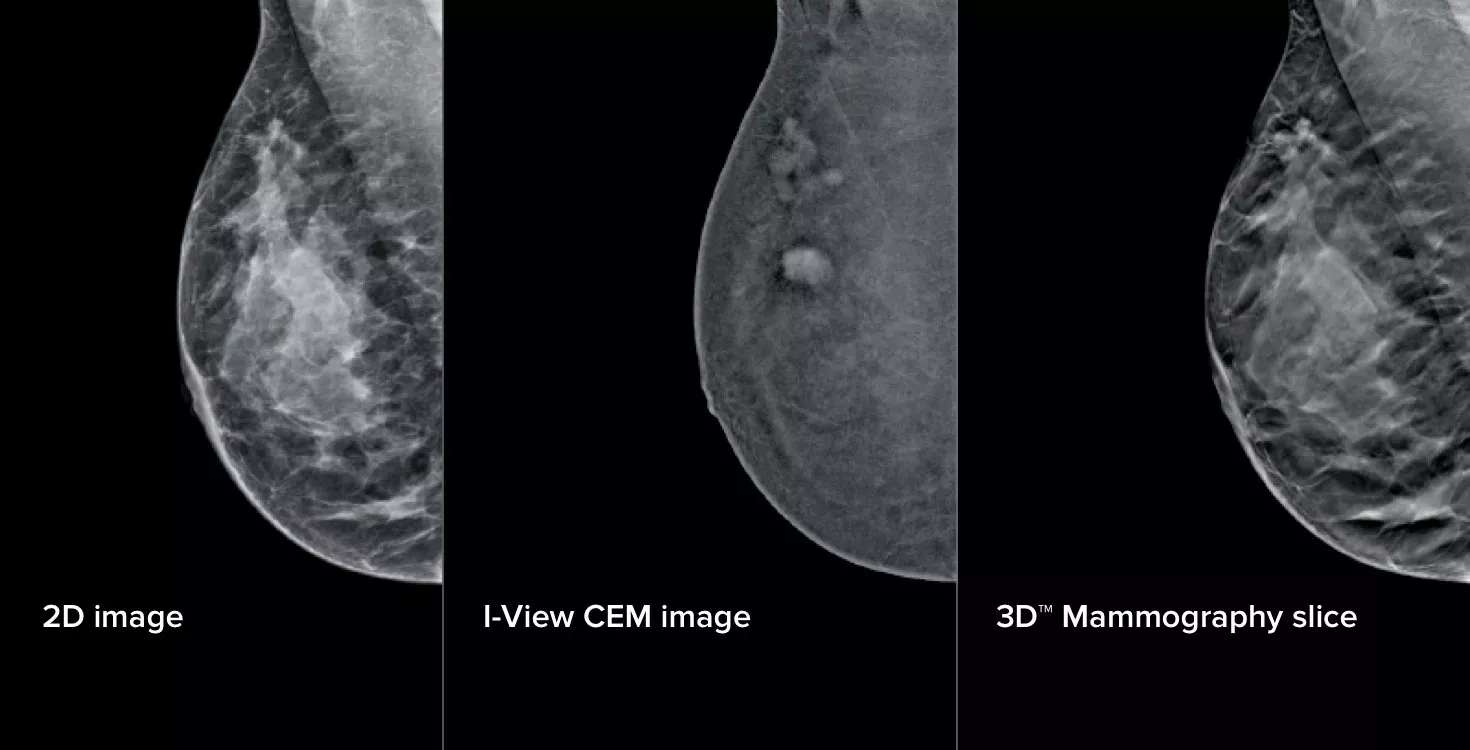

Three different x-ray images

Turn the invisible into visible by using functional imaging.

Hologic’s powerful contrast mammography and biopsy solutions, including the Affirm® upright biopsy system, I-View® 2.0 Contrast Enhanced mammography software, and Affirm® contrast biopsy software, provide smart tools to confidently guide the clinical pathway through screening to diagnosis and biopsy.